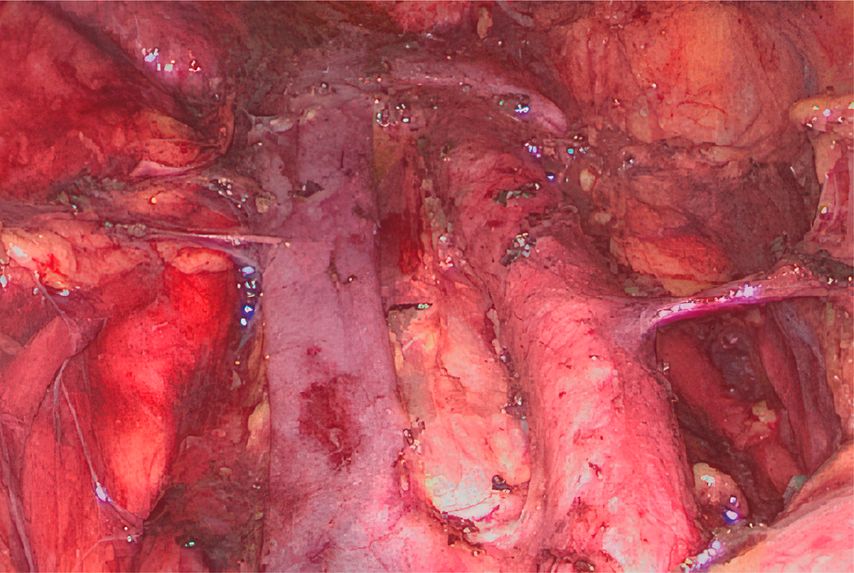

Die Chirurgie kann im Rahmen des Stagings auch durch eine minimalinvasive paraaortale Lymphadenektomie eine Rolle spielen (Abb. 2). Die falsch negative Rate für paraaortale Lymphknotenmetastasen reicht bei PET-CT-positiven pelvinen Lymphknoten und negativen paraaortalen Lymphknoten bis 20%. In solchen Fällen, in denen die Bestrahlungsfelder aufgrund eines pathologisch gesicherten Befunds angepasst werden, kann ein chirurgisches Vorgehen in Betracht gezogen werden.

Eine Chirurgie im Rahmen des Stagings hat nur dann Sinn, wenn die erwarteten Vorteile einer positiven Exploration mögliche negative Effekte derselben überwiegen. Eine laparoskopische paraaortale Lymphonodektomie ist in erfahrenen Händen eine sichere Operation, kann aber ernste Komplikationen verursachen, die den Beginn der primären onkologischen Behandlung, nämlich die Radiochemotherapie, verzögern können. Eine prospektive randomisierte Studie rekrutiert aktuell Patientinnen mit lokal fortgeschrittenen Zervixkarzinomen, um die Frage der möglichen onkologischen Vorteile des chirurgischen Stagings gegenüber PET/CT zu klären.